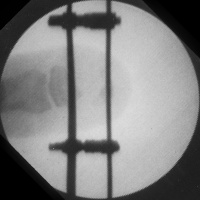

Case 2. Middle phalanx lengthening with proximal metaphyseal osteotomy, distraction and bone graft:

Image Image